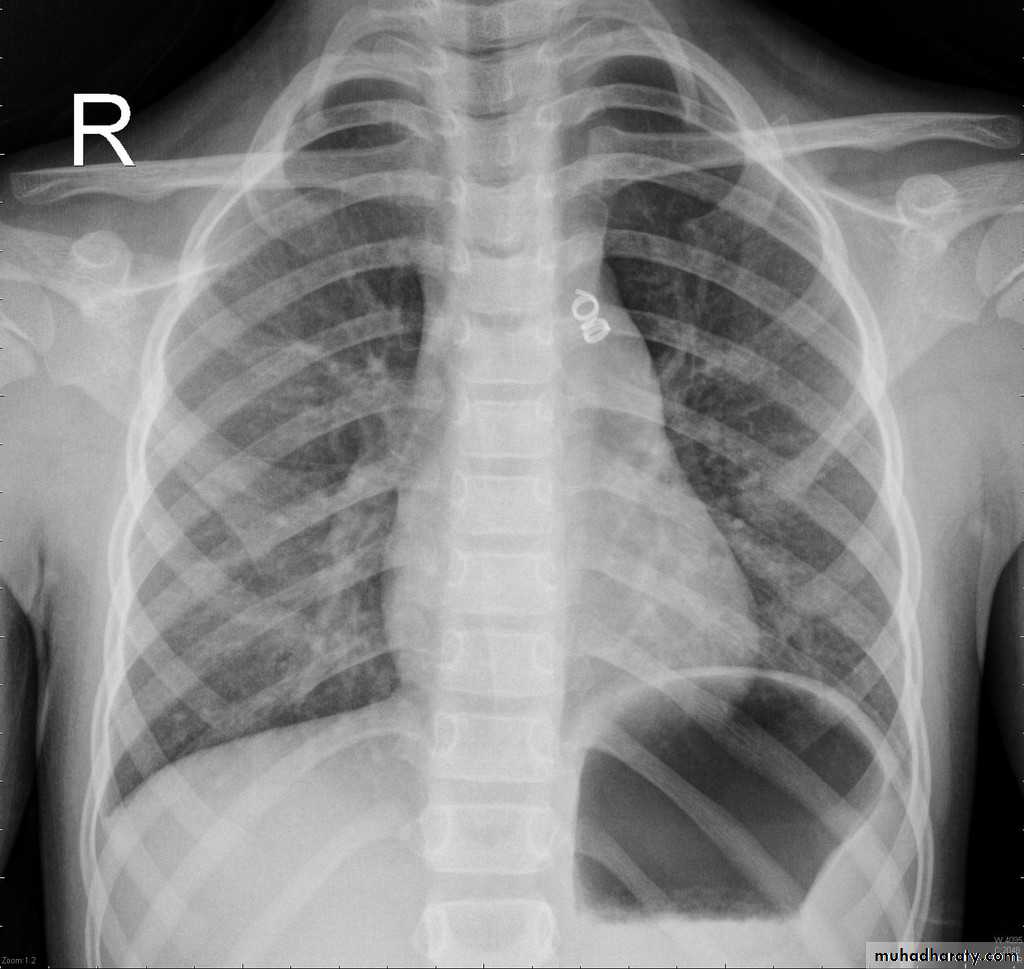

Published on behalf of the European Society of Cardiology. All rights reserved. © The Author 2014. For permissions please email: journals.permissions@oup.comPDA: Investigations: CXR

LV & LA dilatationProminent main pulmonary artery

Plethoric lungs (increased pulmonary vascular markings: arterial and venous)

Prominent aorta

In older patients: the ductus may be calcified